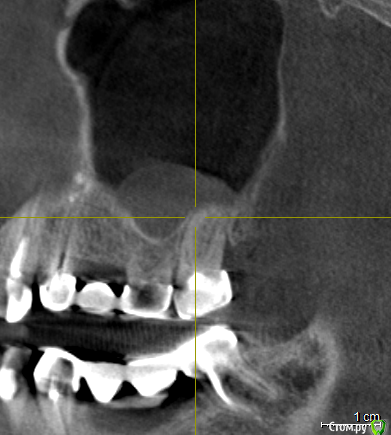

vpaoli Опубликовано 29 февраля, 2016 Поделиться Опубликовано 29 февраля, 2016 (изменено) Посыпались зубы... , что говорят имплантологи-хирурги известно - все удалить и заменить. Хотелось бы получить мнение терапевтов.Под вопросом зубы 16-17, 26-27 и 47. С 45-47 слетел мост, 26-27 после чистки ниткой, у нитки гнилостный запах, над ними в гайморовой пазухе большая киста (видимо как говорят стоматологи онтодогенного происхождения). 47 сидит очень крепко, красноватого цвета, видимо резорцированный и хрупкий. подскажите, можно ли хоть какой то из них лечить?Еще вопрос - над 26, 27 киста в гайморовой пазухе, это опасно или лучше не трогать ? О кисте я узнал только сделав КТ, ранее и сейчас даже не ощущаю ее присутствие.Всех заранее благодарю за высказанное мнение. Изменено 29 февраля, 2016 пользователем vpaoli Ссылка на комментарий

DmitrySH Опубликовано 1 марта, 2016 Поделиться Опубликовано 1 марта, 2016 Что-то КТ скачалось, но при установке ошибку выдает. По этим скринам, 45 точно удаляется. Это без вариантов. У меня есть некоторые сомнения в 4716 да, возможно удаление, но ракурс не очень удачный. ради него и хотел КТ посмотреть.18. не будет функционировать как зуб.Про мост 47-44 лучше сразу забыть и планировать имплантацию в обл 46, 45. 1 Ссылка на комментарий

vpaoli Опубликовано 3 марта, 2016 Автор Поделиться Опубликовано 3 марта, 2016 (изменено) Еще небольшой вопрос - что же мне делать с 45-47. Думаю ставить мост на имплантах 45-47 ( 46 искуccтвенyый) . Почему мост ? Потому, что 46 нет давно и альвеолярный отросток в этом месте имеет вверху острый угол т.е. нужна тоже пластика кости, а это дополнительные деньги и "страдания моего организма" (высокая температура и др. риски). У меня под 45 внутри дырка после резекции верхушки корня с выходом на край альвеолярного гребня на сторону щеки, я это место даже при надавливании пальцем чувствую, в этом месте раньше был свищь. Т.е. вкручивать имплант особо некуда. По моим соображениям для 45 существует 2 альтернативных решения: 1) заполнение этой дырки и лунки костным материалом и через 4 месяца сверление в этом месте под имплант; 2) удаляется зуб и сразу вставляется имплант вместе с куском моей аутокости на границу гребня со стороны щеки или еще как то ...Я склоняюсь к 1) т.к. никуда не спешу и желаю надежности .Правильно я понимаю, что 2) гораздо дороже по деньгам и ничуть не надежнее, чем 1) ? Изменено 3 марта, 2016 пользователем vpaoli Ссылка на комментарий

DmitrySH Опубликовано 3 марта, 2016 Поделиться Опубликовано 3 марта, 2016 Вполне логично рассуждаете, но эта тема уже для хирургического раздела. Ссылка на комментарий